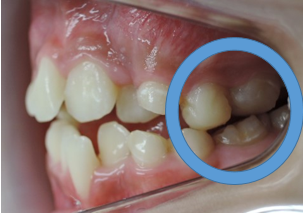

よく診る、難しい症例(奥歯の隙間)

歯列不正

歯を抜かないと治療出来ないと言われた方に。(歯並びが悪い)